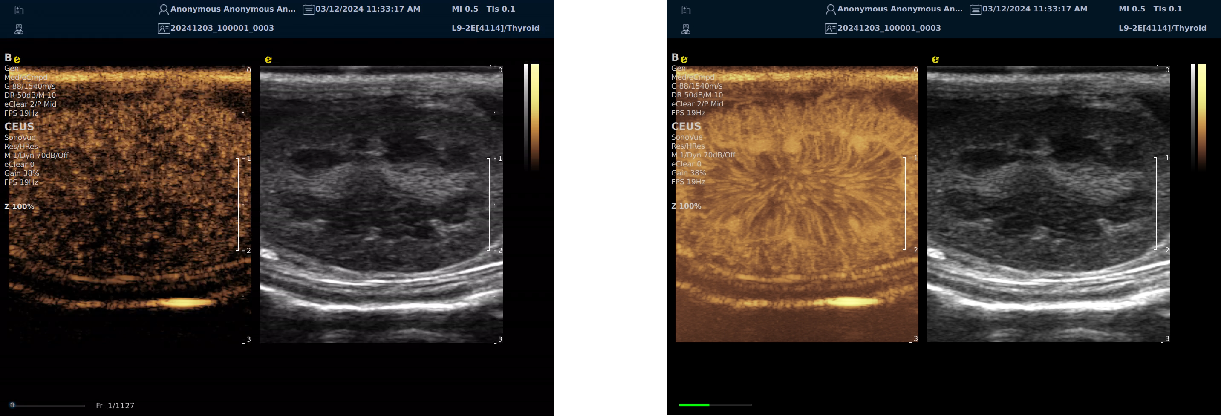

超声造影

image.png

医生可以更准确地识别和评估肿瘤、炎症、血栓等病理变化,从而提高诊断的准确性和可靠性

可以实现实时监测,特别是在手术过程中,帮助医生即时评估治疗效果和发现潜在问题

可以提供关于血流动力学的重要信息,例如评估血管的通畅性、血流速度和分布情况,这对于诊断动脉硬化、栓塞等疾病非常有帮助